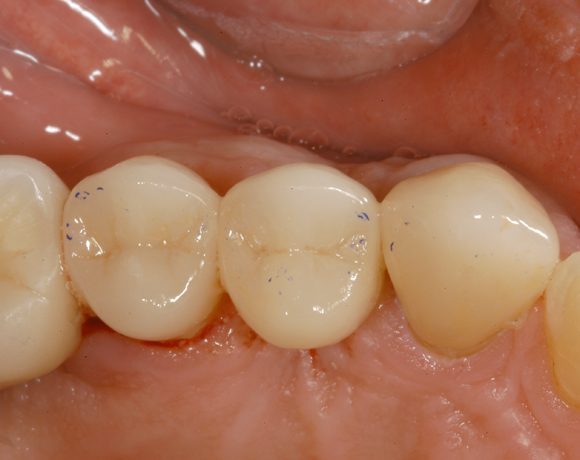

Bei diesem Patienten wurden die Nachbarzähne und das Implantat vollkeramisch versorgt.